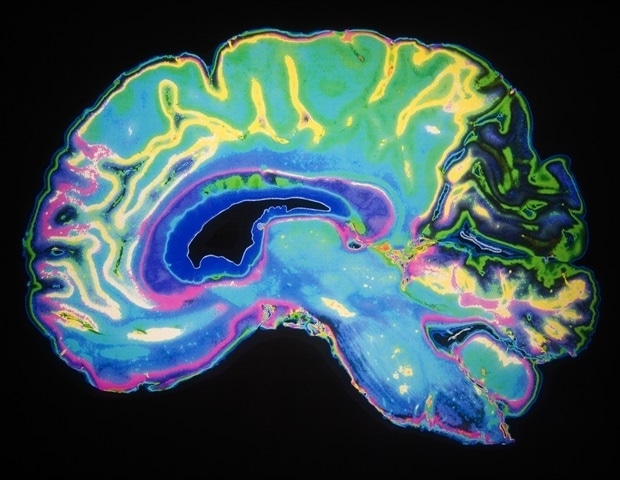

A 20-year-old student from Kinross, Scotland, is defying the odds after battling a rare brain cancer known as anaplastic pleomorphic xanthoastrocytoma (APXA). Joscelyne Kerr was diagnosed in 2023, marking the first recorded case of this particular cancer in Scotland. After undergoing high-risk surgery at just 18, followed by chemotherapy and radiotherapy in 2024, Joscelyne faced the grim reality that these treatments were not effective.

Brain tumors pose a significant threat, affecting individuals of all ages and resulting in more fatalities among those under 40 than any other form of cancer. Alarmingly, only one percent of national cancer research funding has been allocated to brain tumors since 2002, underscoring the critical need for increased awareness and support for research initiatives.